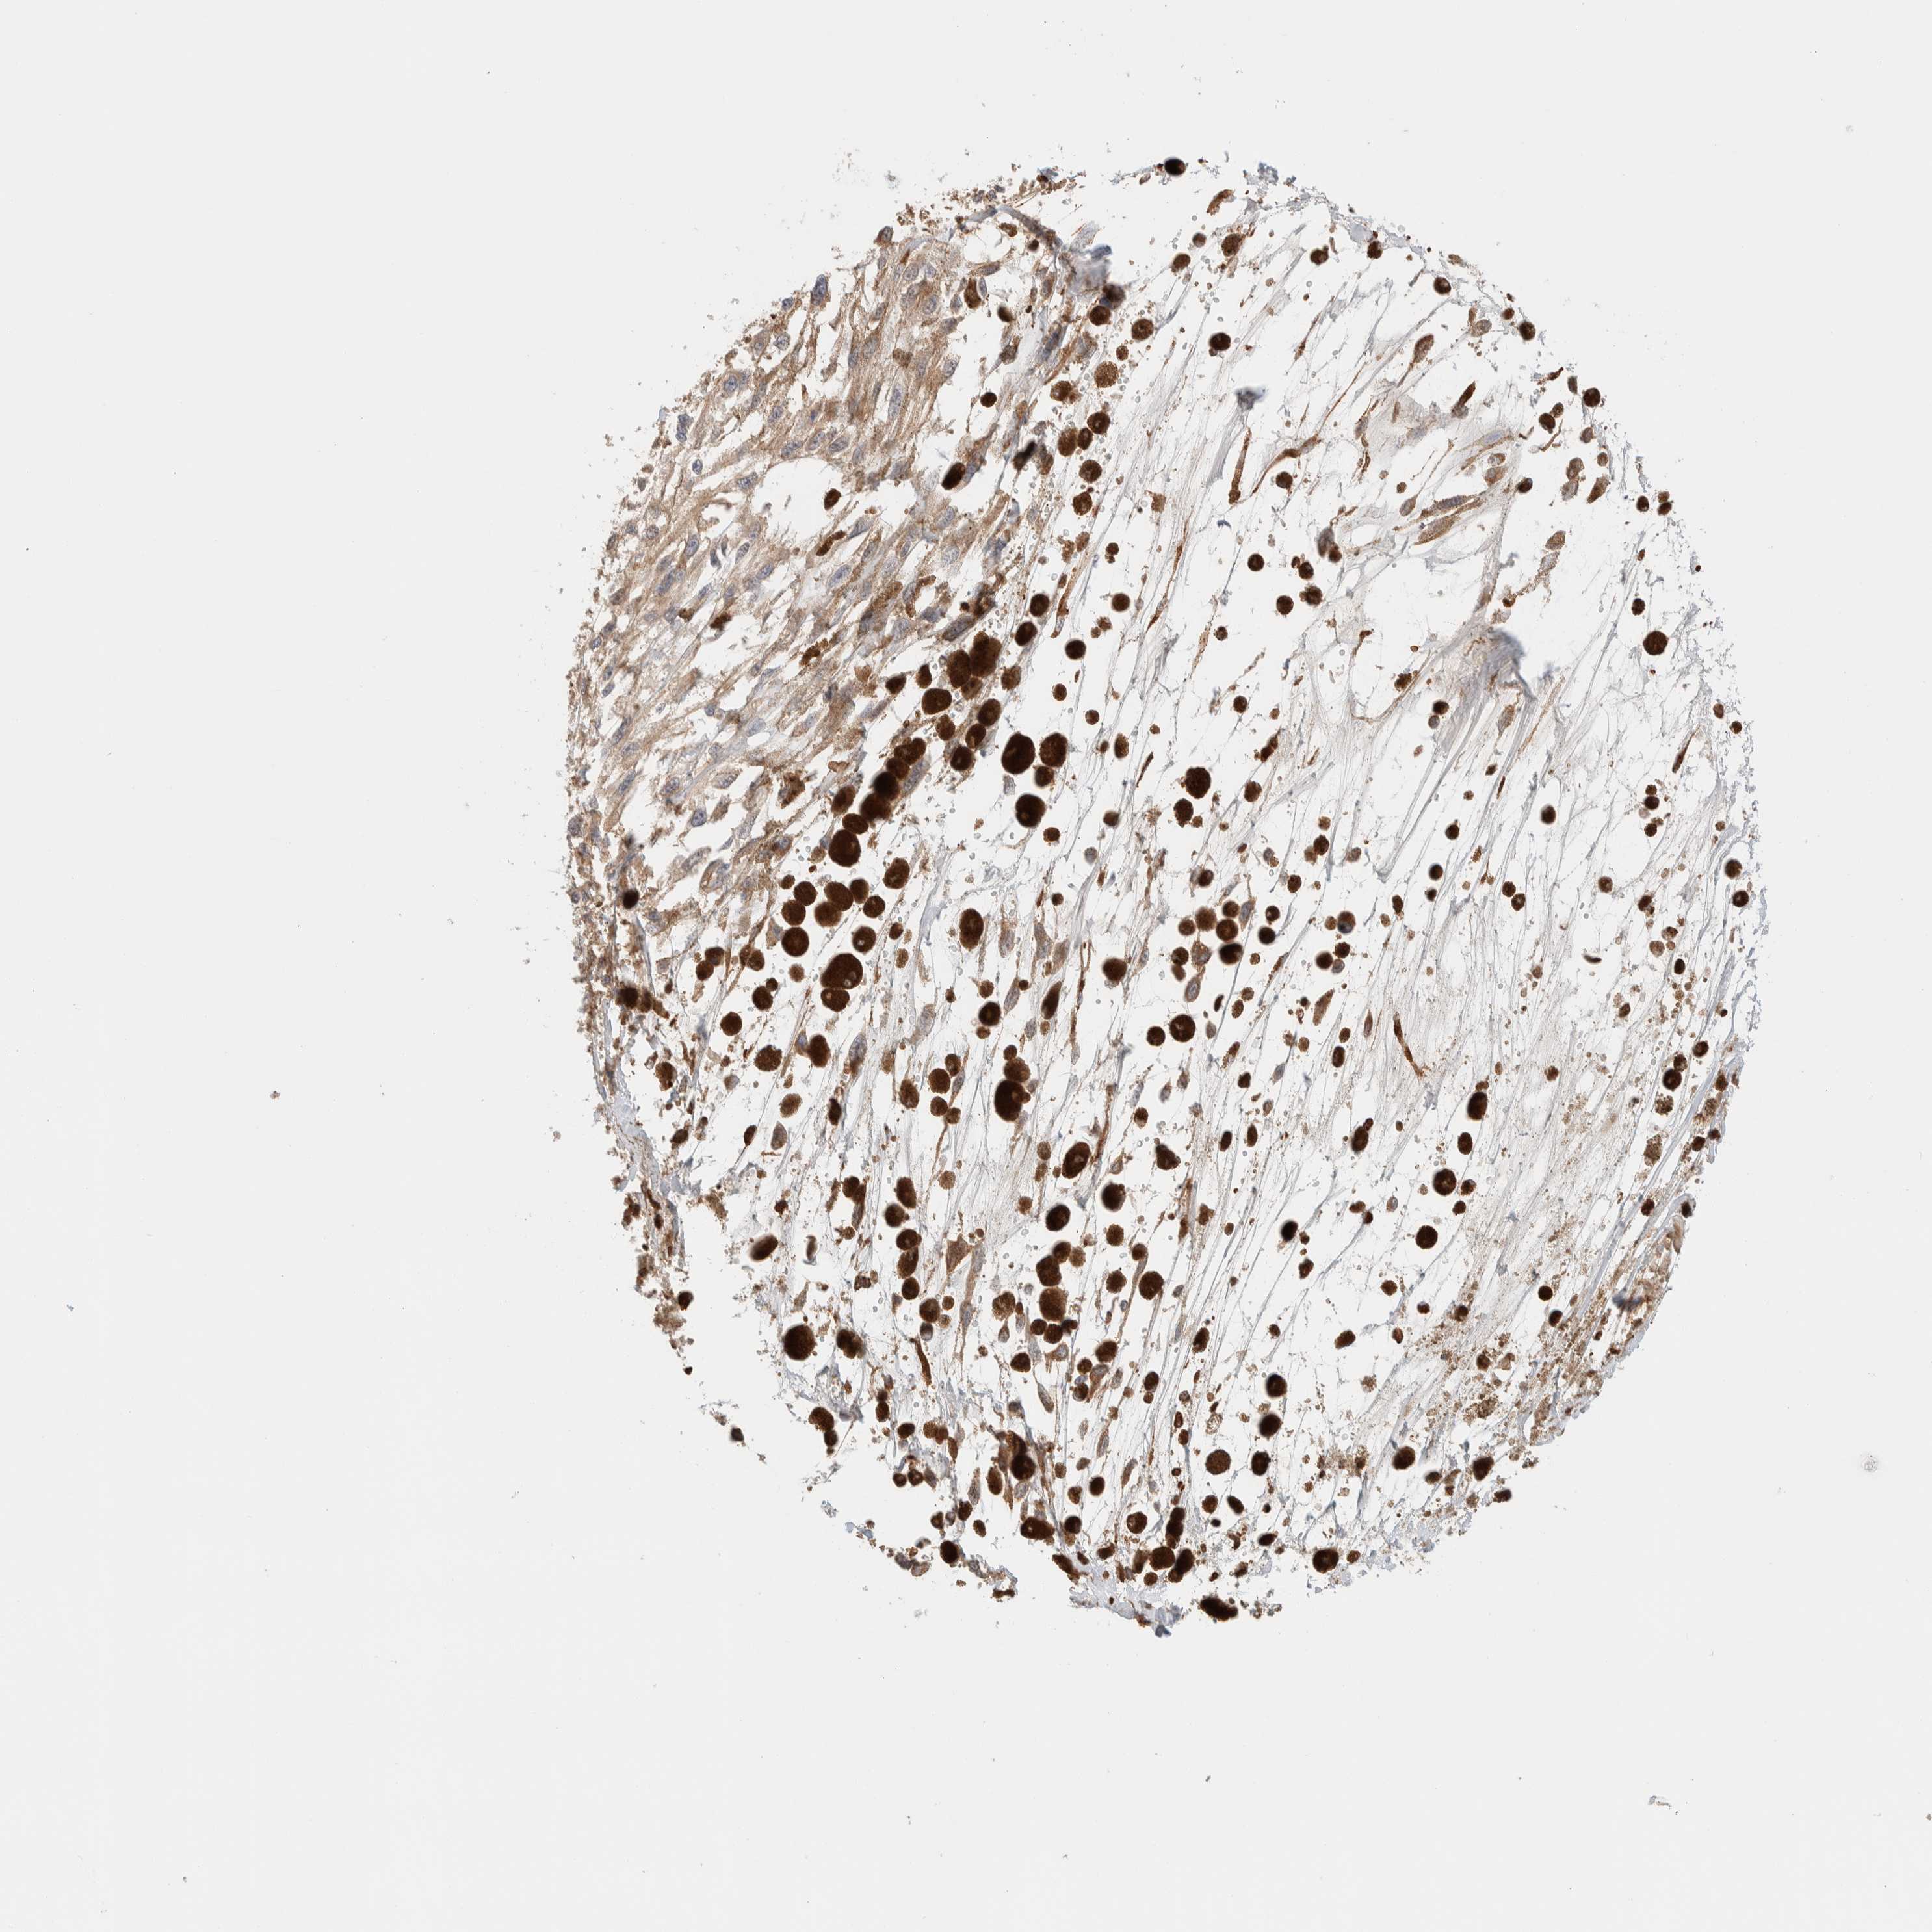

MELANOMA - Protein expressioni

A mouse-over function shows sample information and annotation data. Click on an image to view it in a full screen mode. Samples can be filtered based on level of antibody staining by selecting one or several of the following categories: high, medium, low and not detected. The assay and annotation is described here.

Note that samples used for immunohistochemistry by the Human Protein Atlas do not correspond to samples in the TCGA dataset.

Antibody stainingi

Antibody staining in the annotated cell types in the current human tissue is reported as not detected, low, medium, or high, based on conventional immunohistochemistry profiling in selected tissues. This score is based on the combination of the staining intensity and fraction of stained cells.

Each image is clickable and will lead to virtual microscopy that enables deeper exploration of all samples and also displays staining intensity scores, fraction scores and subcellular localization as well as patient and tissue information for each sample.

Antibody HPA021658

Staining

High

Medium

Low

Not detected

Intensity

Strong

Moderate

Weak

Negative

Quantity

>75%

75%-25%

<25%

None

Location

Nuclear

Cytoplasmic/membranous

Cytoplasmic/membranous,nuclear

Malignant melanoma, NOS

Malignant melanoma, Metastatic site